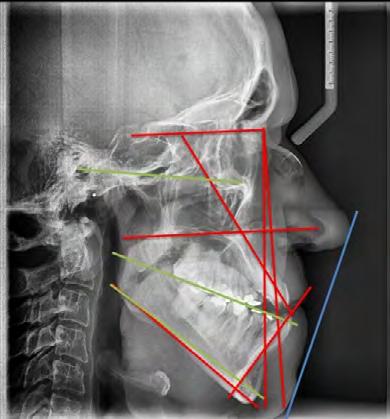

En la radiografía lateral de cráneo tenemos (Figura 7) la clase III esquelética con un ANB de -1, hiperdivergencia, aumento de la altura facial inferior, proclinación de los incisivos superiores con 1 a plano palatino de 133°, línea roja sobre la longitud del incisivo superior.

La radiografía lateral de cráneo en la Figura 11, se observa un ANB de 2° líneas rojas debido al avance del maxilar, una retroclinación del incisivo inferior a 76° líneas amarillas y mejoría de 1-maxilar a 122° líneas azules.

Paciente femenino de 45 años acude al CESO y se le realiza una valoración para recibir tratamiento de ortodoncia. Es diagnosticada con síndrome de Crouzon. En los estudios de inicio extraorales observamos (Figura 1):

Estudios radiográficos iniciales

En la radiografía panorámica (Figura 5) nos muestra los 22 organos dentarios presentes, así como múltiples restauraciones dentales. Se aprecia la pérdida de hueso alveolar, las mallas quirúrgicas a nivel de órbitas y el 23 retenido en paladar.

el equipo multidisciplinario se inició el tratamiento con expansión controlada maxilar. La telerradiografía y la radiografía panorámica brindaron imágenes craneofaciales de suma importancia para planear e iniciar adecuadamente el procedimiento.